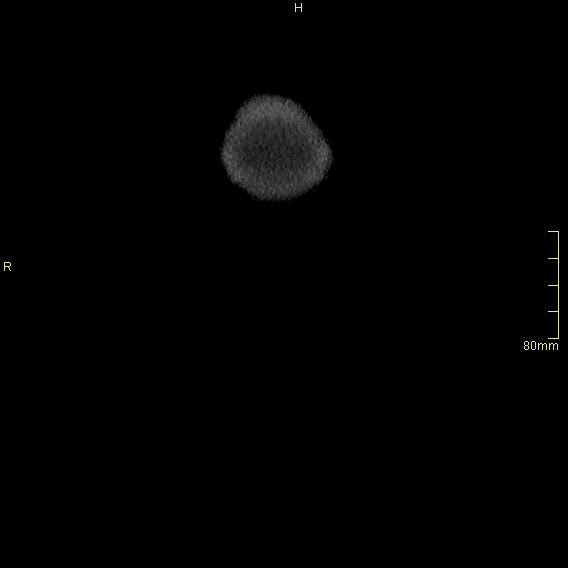

For patients over the age of 40, a non contrast KUB, and seperate nephrogenic and excretory (delayed) phases will be performed. For all patients under the age of 40, a non contrast KUB and a COMBINED dual nephrogenic/excretory phase will be performed. Image examples of this can be seen below.

Under 40 Years of Age

CT Urogram- Nephrogenic + Excretory Phase (Axial)

CT Urogram- Nephrogenic + Excretory Phase (Coronal)

CT Urogram- Nephrogenic + Excretory Phase (Sagittal)